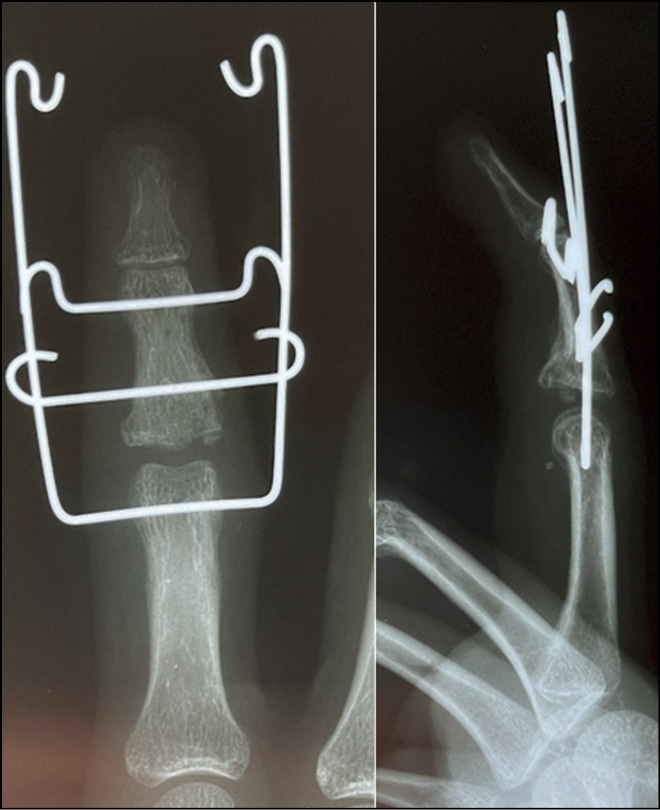

Fig. 26. X-ray control after surgery. Suzuki pins and rubber traction system.

Fig. 27. Appearance after surgery. Suzuki pins and rubber traction system.

During 2021−2022, 26 patients (23 men and 3 women) with fracture dislocation of the middle phalanx base of triphalangeal fingers of hand in the acute period of trauma sought care. The average age was 31 years (16–46 years). The mechanism of injury was axial direction of force (impact) with rear deviation. All patients underwent preoperative diagnosis: radiography and clinical assessment of the amplitude of motion in the joint. Avulsive (detached) fractures of the palmar edge of the middle phalanx base with its dorsal subluxation were determined by radiologic signs. According to the Eaton classification, the patients were categorized as group IIIa. In all cases, the amplitude of movements in PIP joints was sharply limited by pain syndrome. Pain syndrome at the moment of attempted flexion in the joint was from 6 to 8 points on VAS. It was decided to treat all these patients with fixation of the injured finger in the Suzuki distraction-reposition external fixation apparatus (Figs. 24−29). This apparatus was described by Y. Suzuki in 1994 and represents t system of intraoperatively modeled three Kirschner spokes connected by rubber ties [8].

Intraoperatively, a 1.2 mm Kirschner spoke was inserted through the head of the proximal phalanx along the axis of rotation in the PIP joint (axial), with the ends of the spoke bent at 90°. A similar spoke is passed through the head of the middle phalanx along the axis of rotation in the distal interphalangeal joint; the ends of the spoke are also bent at 90°. Opposite bends (loops) are created at the ends of the curved shoulders of the spokes, ensuring a distance of 2.5 cm between them. Next, the third (repositioning) spoke is passed through the base of the middle phalanx as proximal as possible to the fracture zone; it is displaced to the rear relative to the phalanx axis and should pass under the shoulders of the axial spoke. Elastic rings, each 1 mm thick and cut from the rubber injection unit of an intravenous infusion system, are stretched over the bends of the first two predissected spokes. The degree of tension (distraction) of the spoke system (indicated by the number of elastic rings) is determined intraoperatively radiologically, based on size of the interarticular gap. Repositioning component of the system is accomplished by passing the middle phalanx base spoke displaced to the rear under the axial spoke. The last guided spoke is bent around the axial spoke to prevent displacement from under it but not to limit sliding between them.

Fixation in this system was carried out for 4 weeks. On day 1, the patient is trained to develop movements in the PIP joint passively. On day 2, the patient begins to perform active movements in the joint, and a radiologic control study is conducted to determine the degree of distraction and the need for its correction. It is acceptable to increase the joint gap to 4−5 mm, but the most desirable is 2−3 mm. During the outpatient phase of treatment, the patient is recommended to develop passive/active movements three to five times a day.